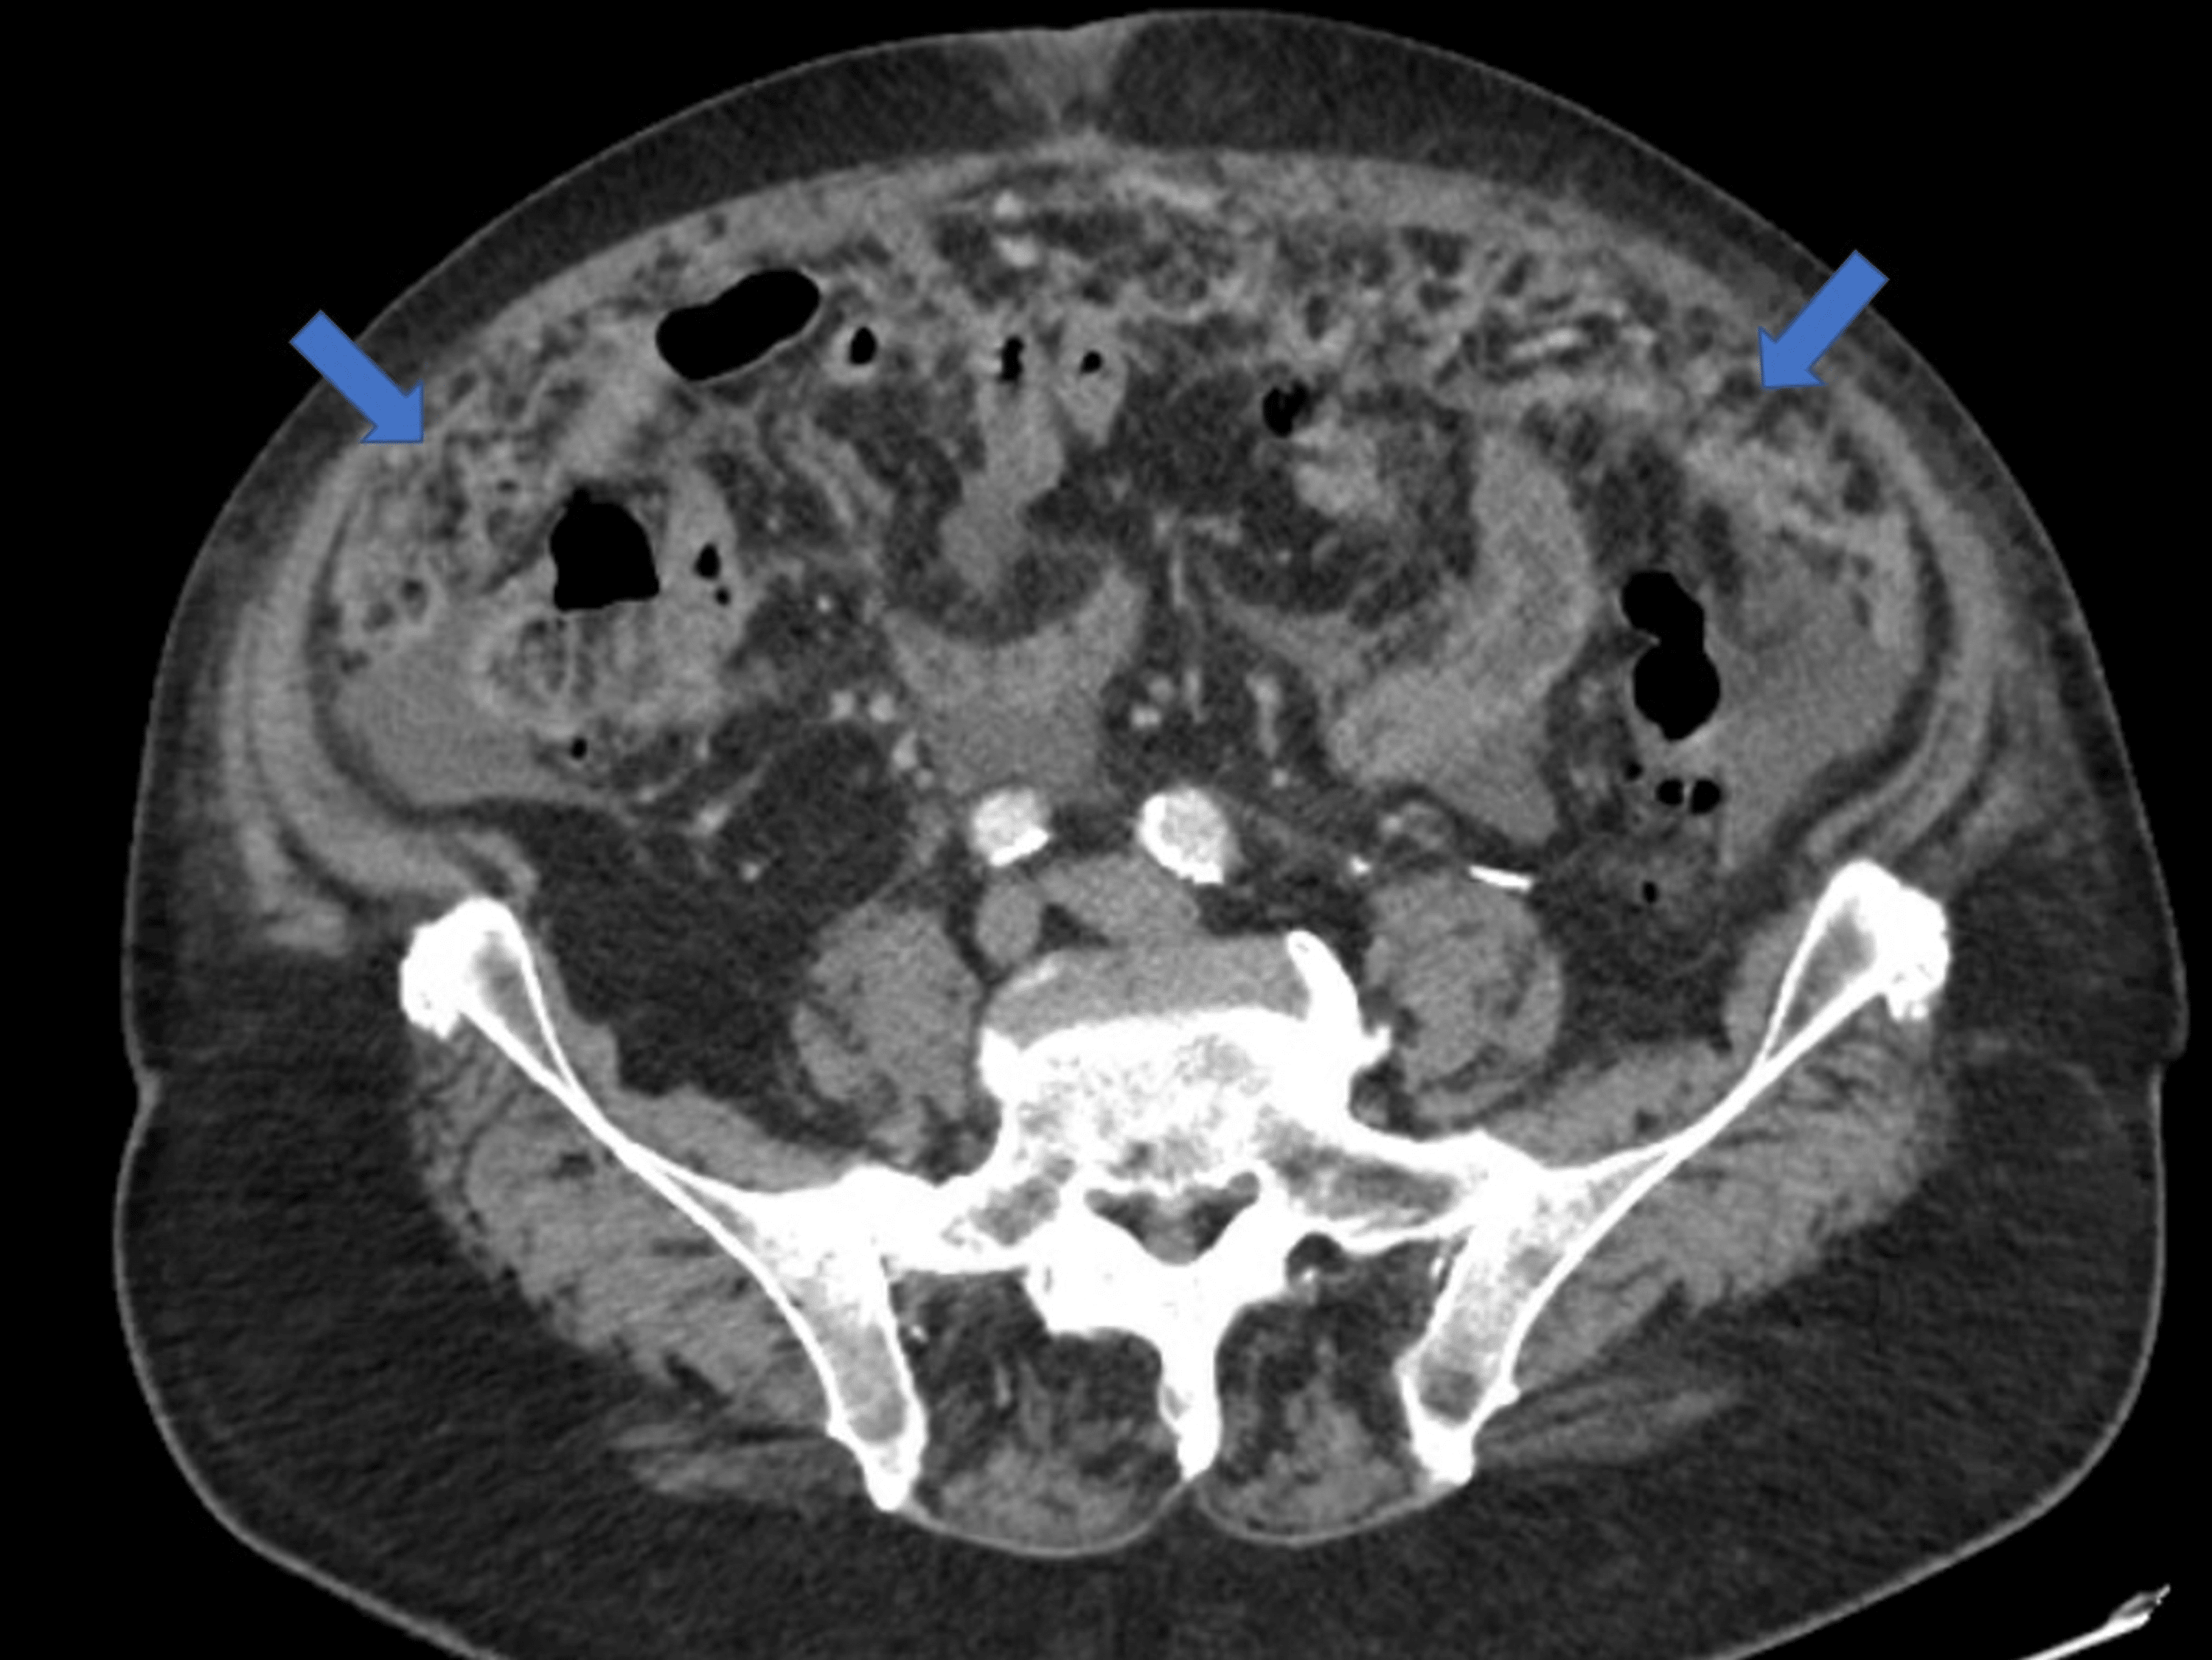

Patterns of peritoneal spread of tumor in the abdomen and pelvis

From www.wjgnet.com

Patterns of peritoneal spread of tumor in the abdomen and pelvis Abdominal Carcinomatosis Definition Peritoneal carcinomatosis is most often. Peritoneal carcinomatosis is a form of cancer that affects the peritoneum. The peritoneum is a thin membrane that covers most abdominal organs and lines the abdominal cavity. Cancer that has spread to the lining surfaces of the peritoneal (abdominal) cavity from ovarian cancer, primary colorectal cancer, appendiceal. It’s sometimes called primary peritoneal. Peritoneal cancer is. Abdominal Carcinomatosis Definition.